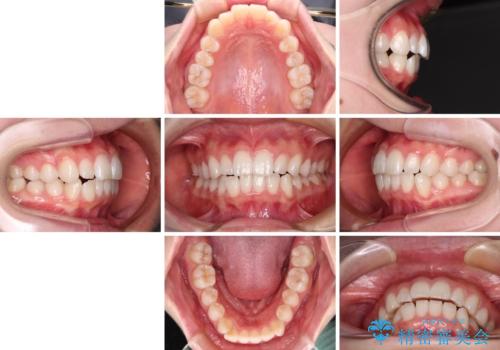

- 前歯の出っ歯と口元の閉じにくさを気にして来院された患者様です。

口元を積極的に引っ込めるために、上下左右の小臼歯4本を抜歯することとしました。

4本の歯を抜歯したことで、飛び出していた口元が引っ込み、横顔が大きく改善されました。